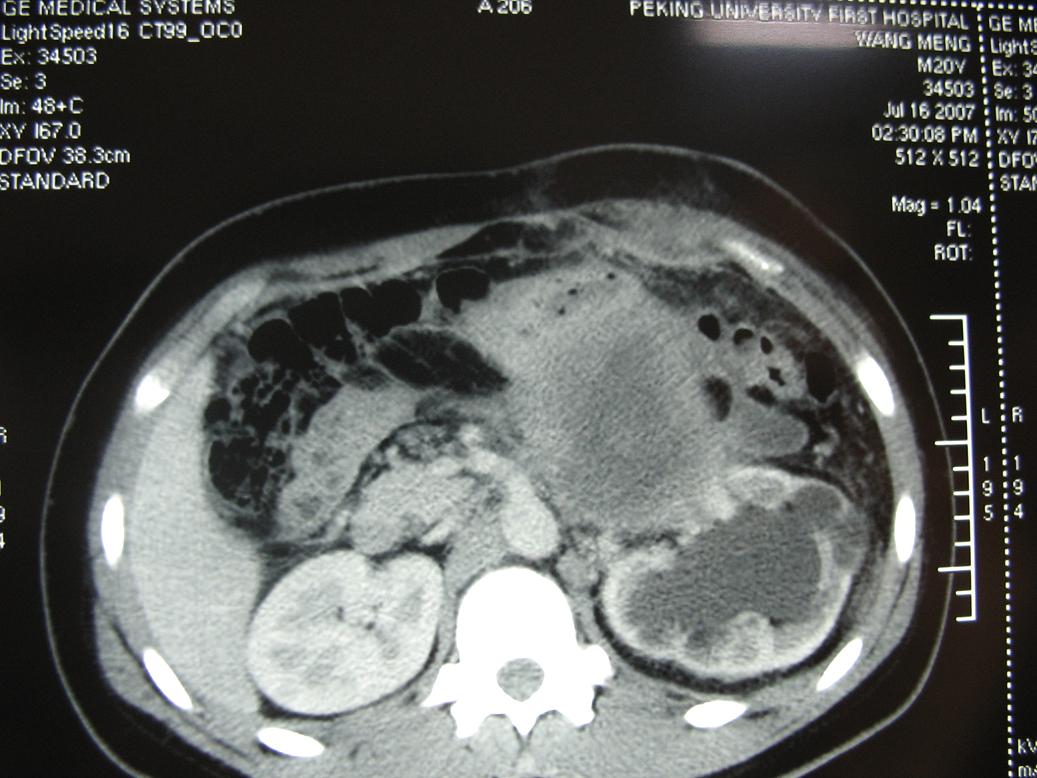

m20,发现腹部肿物二月.

2、左侧腹膜后囊实性占位性病变,有完整包膜,周围脏器及血管呈受压移位改变,左肾积水,肾实质变薄,增强扫描示病变包膜有强化,因图片太少,实性部分是否强化不好判断。

3、诊断:结合病人年龄,左肾改变考肿虑为输尿管受压肾积水时间长,左肾实质萎缩,病变未见明显外侵征象,本人首先考虑为神经源性瘤囊变可能性大。

定位肿瘤在腹膜后没问题,包膜完整与左肾门及腹主动脉关系密切。腹膜后未见明确异常增大淋巴结,左肾积水增大,但要考虑肠间质瘤就不是腹膜后的了,手术至少要普外和泌尿外科协作,术前必须把肿瘤血供再搞清楚一点才行,肿瘤性质和组织学来源是病理的事,之后影像再回头学习。

结果收到,肿块较大,密度不均,实性部分有强化,包绕腹主动脉推挤左肾,左肾集合系统受压改变,病灶长轴与腹主动脉平行,支持副神经节瘤,但不典型。